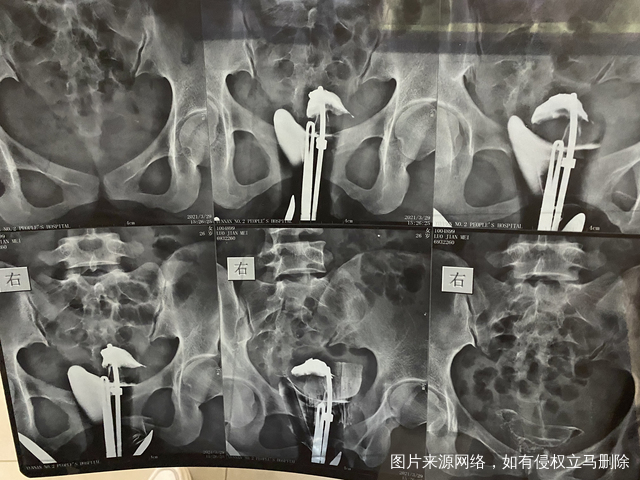

备孕多年未怀孕原发不孕本月做输卵管造影报告显

做完输卵管造影第六天了小腹还是感觉沉甸甸的如